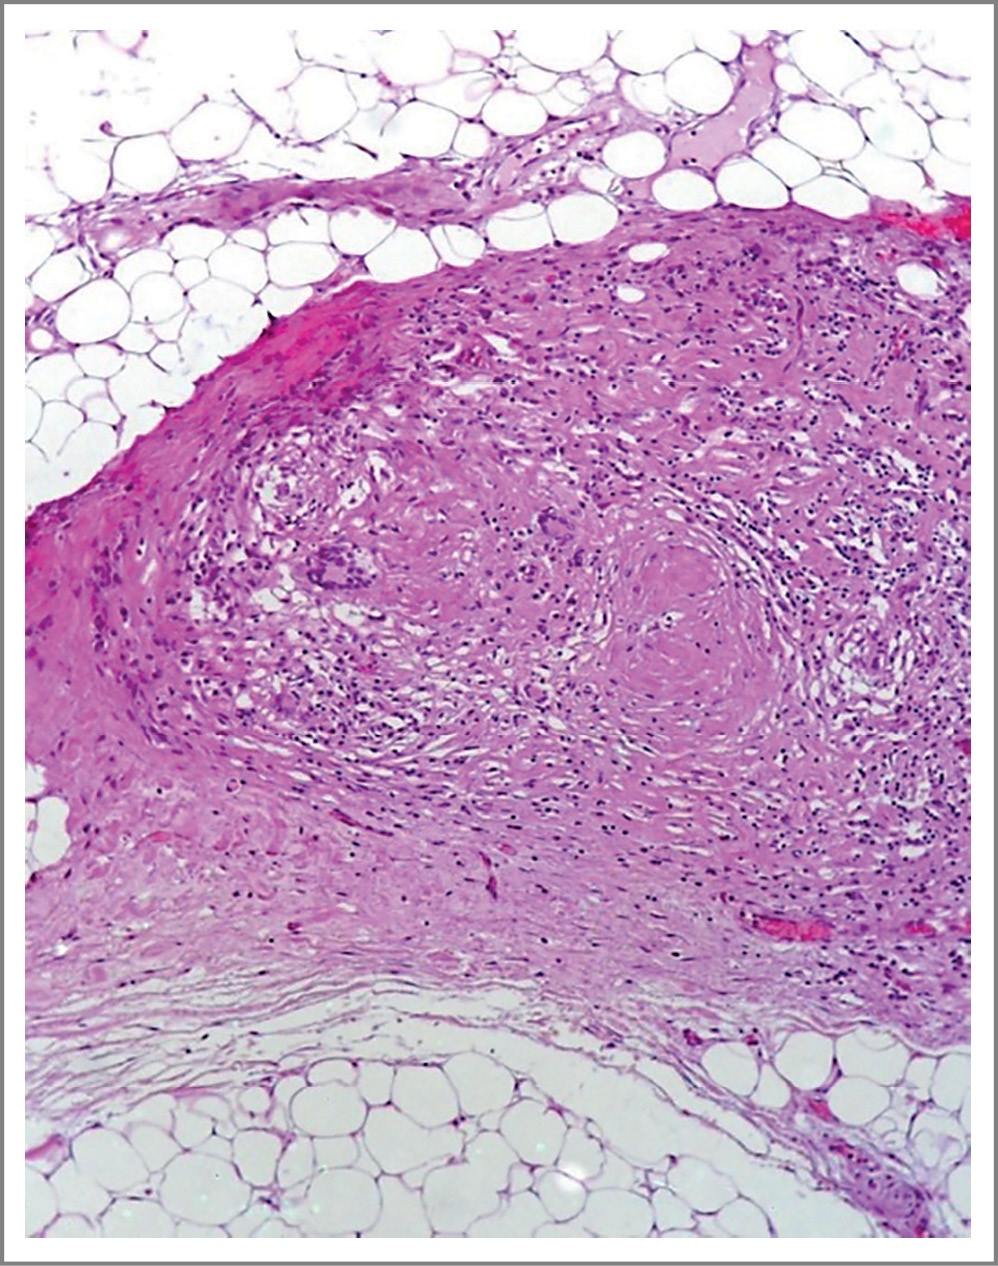

Выполнена резекция петель подвздошной кишки, илеоцекального угла, вскрыты абсцессы малого таза и брыжейки тонкой кишки, проведены санация брюшной полости и формирование концевых илео-асцендостом. В асцитической жидкости обнаружена M. tuberculosis complex. Морфологическое исследование операционного материала выявило в стенке слепой и подвздошной кишки хроническое продуктивное воспаление с образованием множества эпителиоидно-клеточных гранулем с наличием гигантских многоядерных клеток типа Пирогова–Ланхганса, большинство из которых с абсцедированием, а также изъязвление слизистой оболочки и образование сквозных дефектов до висцеральной брюшины с нейтрофильной инфильтрацией, фиброзом и наложением фибрина на поверхности брюшины. В лимфатических узлах имелись эпителиоидно-клеточные гранулемы с участками казеозного некроза и наличием гигантских многоядерных клеток типа Пирогова–Лангханса. Морфологическая картина с учетом результатов ПЦР-исследования асцитической жидкости характерна для ТБ слепой и подвздошной кишки, ТБ лимфатических узлов брыжейки, с развитием перфорации кишки и формированием разлитого фибринозно-гнойного перитонита (рис. 3).

Рис. 3. Казеозные гранулемы в брыжейке подвздошной кишки.

Fig. 3. Caseous granules in the mesoileum.